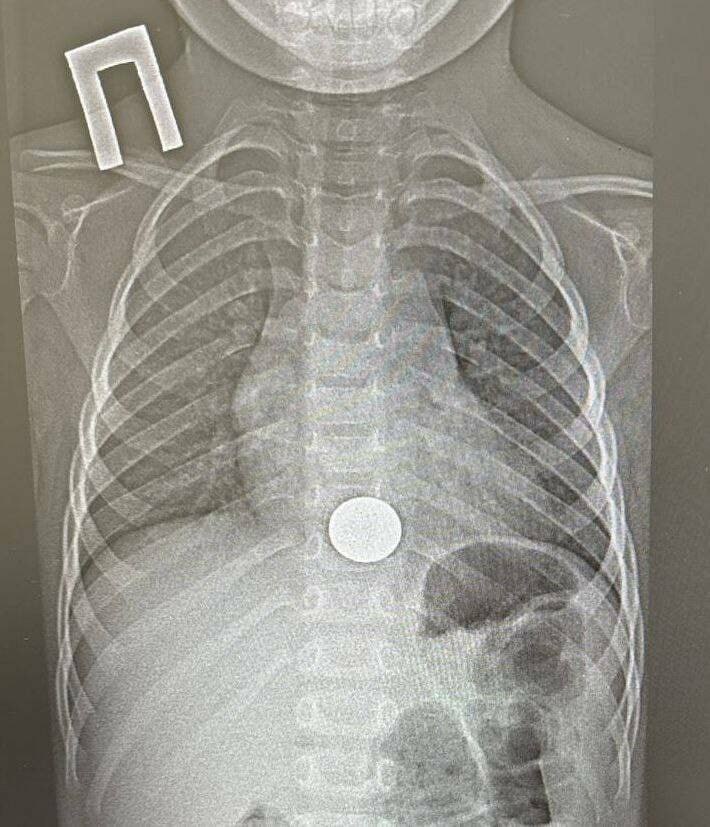

В Нижнекамске врачи детской районной больницы извлекли монету из пищевода ребенка

Детский хирург, врач-эндоскопист Игорь Шогоров удалил инородное тело с помощью эндоскопа. Манипуляция заняла около минуты.

После процедуры ребенка для наблюдения перевели в хирургическое отделение, а уже на следующий день, убедившись в его удовлетворительном состоянии, выписали.